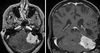

What is this?

Benign meningioma of the left cerebellum

- Dural tails characteristic of meningioma

- Cause problems by mass effect

- Surgical resection or radiation to shrink